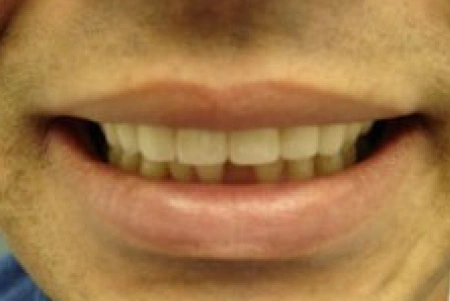

Before

Before: Patient unhappy with six Upper Anterior teeth. The edges are uneven, the gumline is uneven on the two central incisors, and the color/shade is not uniform. The two lateral incisor teeth have been previously restored and are poorly shaped.

After: Smile restored with 6 Upper Anterior Crowns that are properly shaped, gumline is uniform, and color/shade is the same for all 6 incisor teeth.